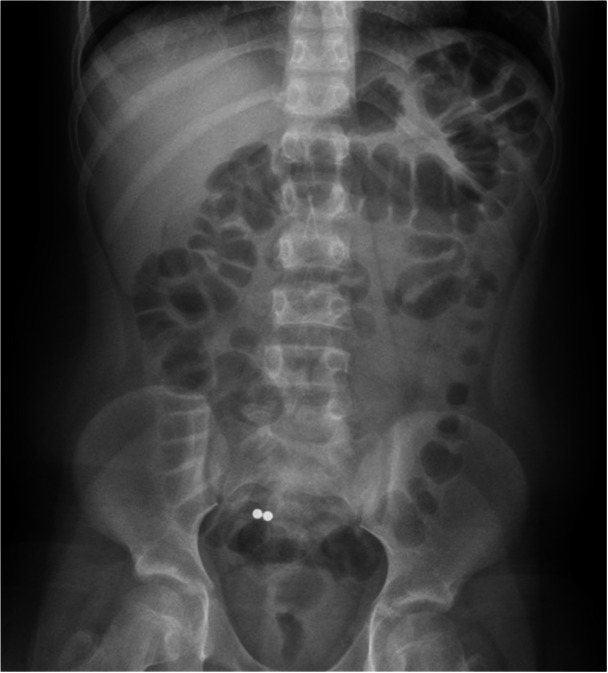

Ingestion of multiple magnets can lead to serious complications, including foreign body appendicitis. Appendicitis usually develops when an object blocks the appendiceal orifice, though outcomes may vary from asymptomatic passage to acute inflammation. While several case reports have documented appendectomy for magnet-induced foreign body appendicitis, and one report described endoscopic removal of magnets in a patient with appendicitis, this case is the first to report successful endoscopic removal of high-powered magnets from the appendix in an asymptomatic child. This intervention potentially prevented the development of appendicitis and the need for surgery. This case highlights the importance of considering foreign body retention in the appendix when objects fail to progress beyond the right lower quadrant.